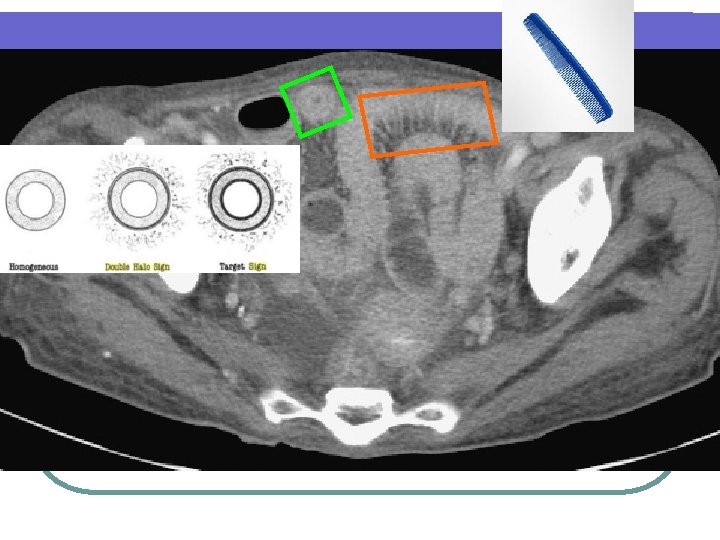

Double halo sign or target sign l Double halo sign = either a higher-attenuation outer ring (muscularis propria) + inner ring of gray attenuation or a higher-attenuation inner layer (submucosa) + outer ring of gray attenuation. Differential Diagnosis — l Idiopathic inflammatory bowel diseases, vascular disorders, infectious diseases, and radiation damage. The uncommon diagnosis in which this pattern occurs is malignancy.

Comb sign l Higher-attenuation l To of vasa recta differentiate active inflammatory condition from lymphoma and metastases, which tend to be hypovascular.